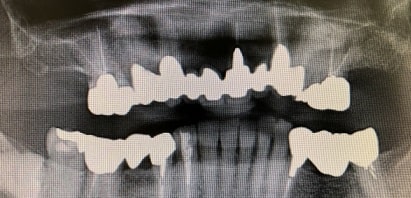

大きな病院で、MRIなどの装置で画像検査をします。

開口障害に長年悩んでいて、最近病院でMRI などを撮って、診察を受けています。

今回初めてMRI を撮った結果、顎関節には何の異常もないことがわかりました。